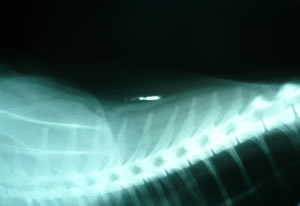

A microchip implant is a tiny integrated circuit placed painlessly under the skin of an animal. The chip, about the size of a large grain of rice, uses passive RFID (Radio Frequency Identification) technology and can be easily read by vets and animal sanctuaries to read data about a pets owner.